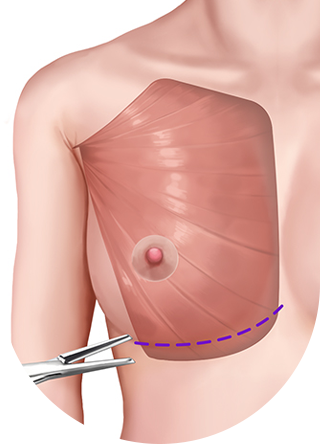

ผ่าตัดส่วนล่างของกล้ามเนื้อหน้าอกส่วนบน

เมื่อกรีดกล้ามเนื้อออก เนื่องจากแรงดึงของกล้ามเนื้อ ทำให้ส่วนบนของกล้ามเนื้อหดตัวและด้านล่างของกล้ามเนื้อจะยึดติดกับด้านล่าง

ดึงส่วนบนของกล้ามเนื้อขึ้น

กล้ามเนื้อส่วนล่างจะยึดติดกัน